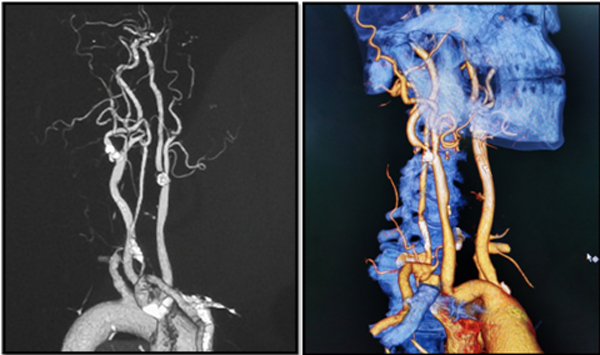

图4 术后复查CTA示右侧椎动脉通畅良好

在麻醉科和手术室同道的共同努力下,右侧椎动脉闭塞复合手术血运重建手术如期进行,尽管术中发现闭塞部位斑块质地较硬,位置较深在,王东海教授还是凭借精湛的技艺熟练地将椎动脉起始部内膜斑块完整剥下(图三A),但是手术中未见到颅内明显的返向血流,术中脑血管造影证实椎动脉未通。复合手术的优势在于一期解决开刀和介入所遇到的问题,借助于复合手术室的治疗平台,治疗小组经过努力找到了椎动脉真腔,将微导管(Echelon-10,EV3,美国)输送闭塞远端,并于闭塞阶段内桥接两枚支架(APOLLO,微创,中国),造影见椎动脉通畅(图三B),术中TCD监测显示右椎动脉及双侧大脑后动脉开放良好,前后循环较术前明显改善,但无明显过度灌注。术后复查头颈部血管CTA,见右侧椎动脉开放良好,后循环血管显影良好。